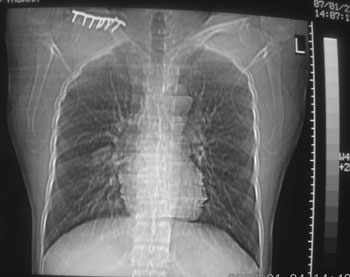

锁骨骨折复查,发现肺内高密度影,行ct检查。

男性,35岁,无任何感觉,无明显发热感冒病史。

右肺下叶背段斑片状阴影,边缘模糊,纵隔内未见肿大淋巴结,病人无发热及感冒史,要考虑浸润型肺结核,可结合ppd检查,或短期抗炎治疗复查。

右肺下叶背段长椭圆型病灶,边缘较规则,无明显分叶征、毛刺,远段未见阻塞征象,病灶较松散,纵隔窗明显小于肺窗,年龄35岁,支气管稍示变窄,纵隔内未见明显肿大淋巴结,这些都不支持肿瘤。病人无任何感觉,无明显发热感冒病史,首先考虑结核(也是结核好发部位),慢性炎症不能完全除外。